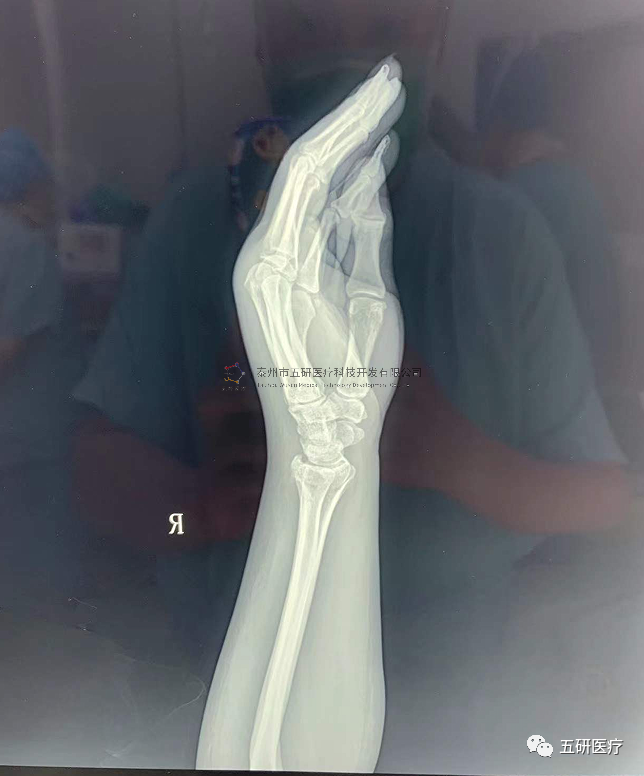

【基本資料】患者,女,61歲

本病例腕架骨折。術(shù)前正側(cè)位片:右橈骨遠(yuǎn)端骨折。